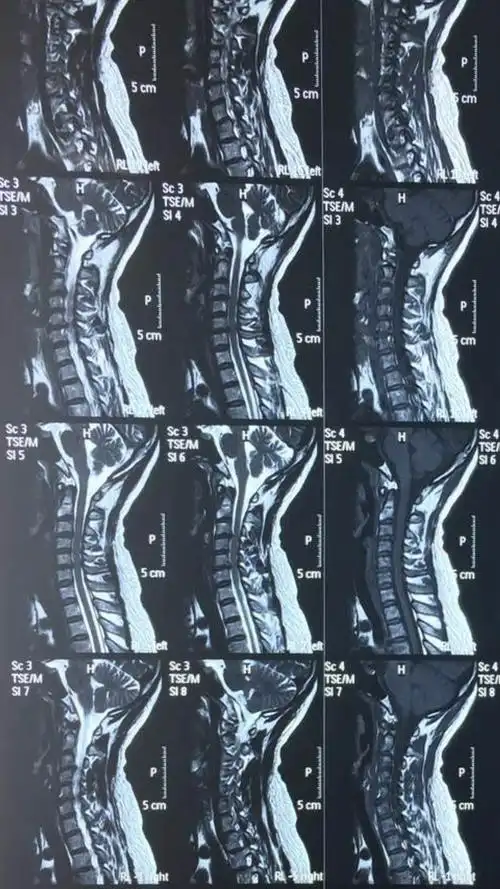

颈椎3456向后轻微突出,前几天有呕吐,很严重吗?今天刚照的核磁.

颈椎病病正骨后出现,脖子一动就有响声,脖子向右转时疼痛,手有麻木,帮

脊髓型颈椎病